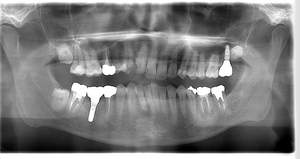

インプラント治療の症例4

レントゲン写真

- Befor

- After

| 年齢 | 50代・男性 |

|---|---|

| 主訴 | 部位:左下6番7番 主訴:左下奥歯腫れて痛い。 |

| 治療内容 | 左下6番抜歯、左下6番7番骨造成、インプラント埋入 |

| 治療費 | 合計:1,232,000円 ・内訳 診断料:55,000円 サージカルガイド2本:66,000円 GBR:110,000円×2本 埋入料:165,000円×2本 静脈内鎮静麻酔:77,000円 2次OPE:22,000円×2本 仮歯:55,000円×2本 上部構造(フルジルコニア):165,000円×2本 (2023年1月現在) |

| 治療期間 | 約8ヶ月 |

| 治療方針 | 元々支台歯に負荷がかかりやすいとされている延長ブリッジを抜歯し、1本単体でしっかりかめるようにインプラントを2本埋入した。骨吸収も進んでいたため、※GBR法で骨造成を同時に行った。 治療と並行して、全顎的な歯周病治療も行い、今後は歯周病が進行しないよう、こまめにメンテナンスに通っていただく。 |

| 特記事項 | ※1 GBR・・・骨再生誘導法。骨の高さや厚みを人工骨や人工膜などを使用し再生する方法 |

| 担当者所見 | 6番は歯根分割された被せ物が7番の欠損部との延長ブリッジとされており、強い咬合と歯周病も相まって負荷がかかり動揺し、歯として機能しなくなったため、抜歯となった。 |